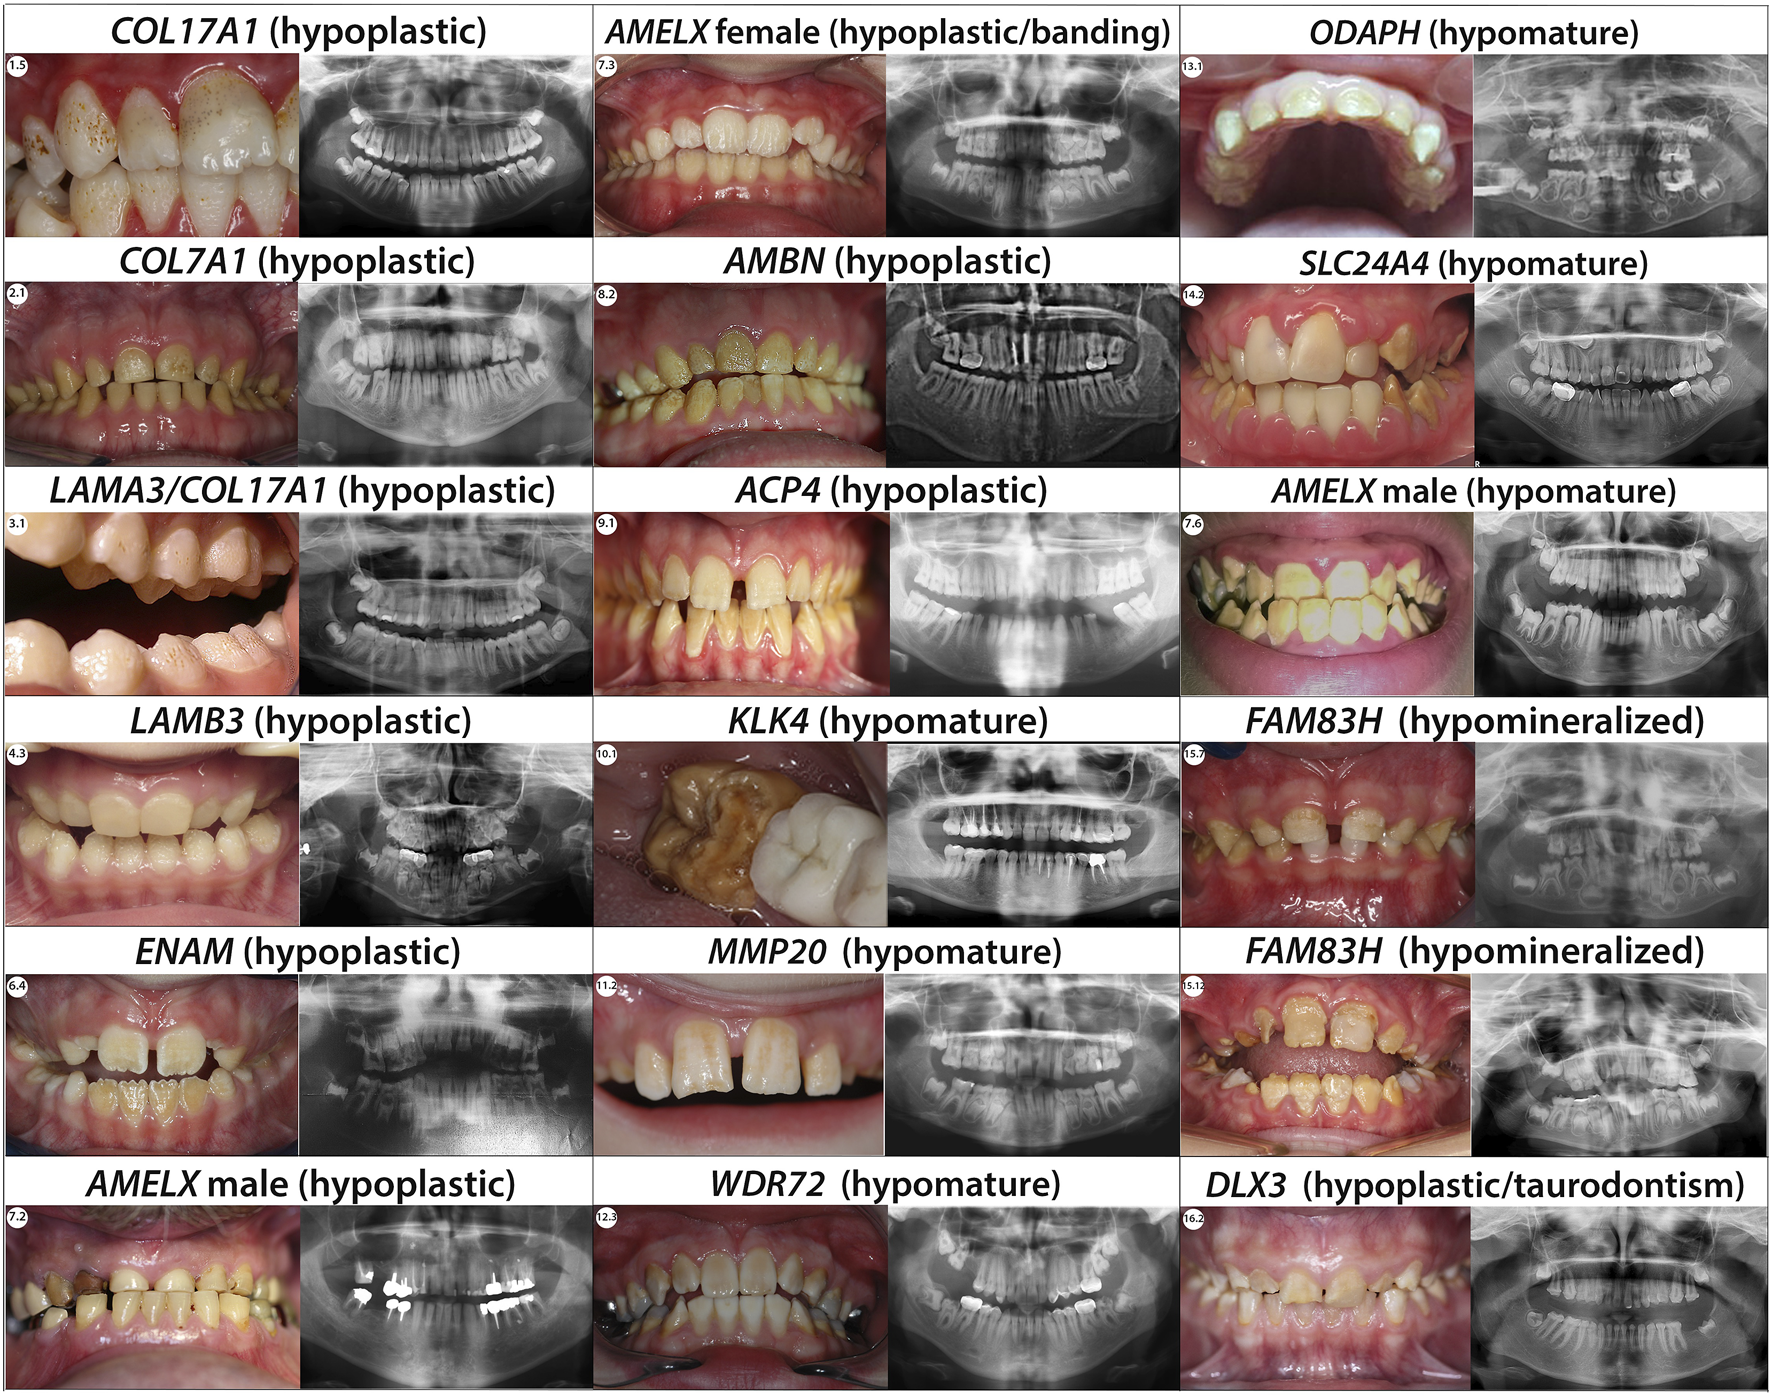

FIGURE 4

Phenotype/Genotype correlation for isolated AI. Typical phenotype/genotype correlation observed in patients presenting with isolated Amelogenesis imperfecta (intraoral pictures and radiographs). Patients who are carrier of AMELX mutations can present with different types of AI. Indeed, the phenotype can be either hypoplastic (severe with almost no enamel in male and with a lyonization banding pattern in female) or hypomature depending on the mutation’s localisation. When the mutations occur in a MMP20 cleavage site the AMELX related AI observed is a X-linked hypomature AI.